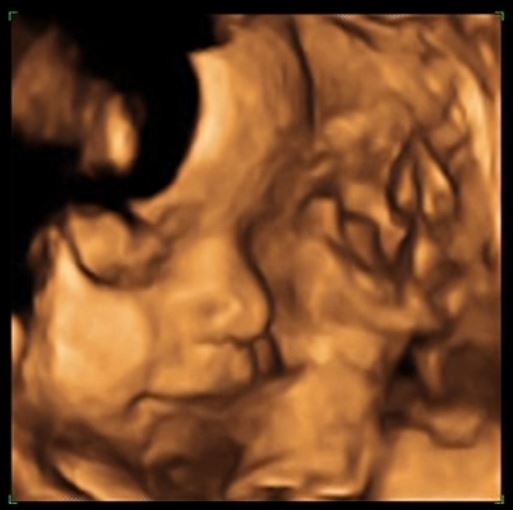

A připojuji foto té naší princezny